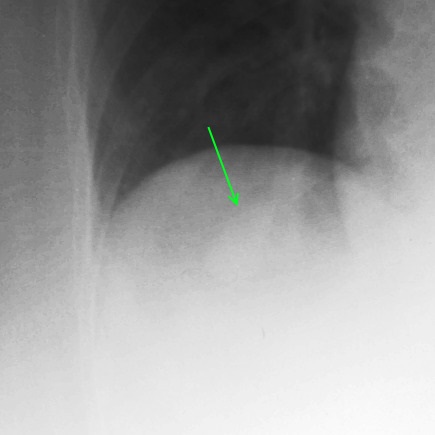

Trouble in the chest, in a lady with a stroke. Surely you can just see the outline of the oval density in the right base through the liver!

The cause of the stroke in this lady is most likely the arteriovenous malformation in the posterior parietal region, where multiple ectatic sections are present which drain into superior sagittal sinus. Thrombus may form in the dilations and lead to a stroke or they could be areas of haemorrhage. However, in this case, the arteriovenous malformations in the lungs could also have been the source of an embolus.